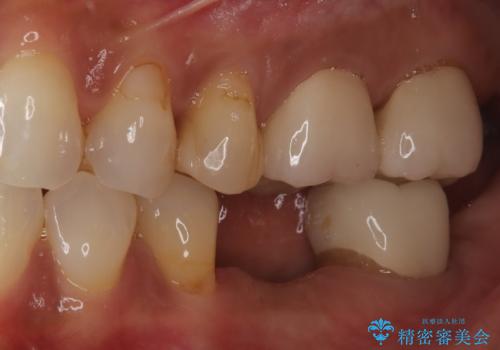

- 歯を破折により失ったため、義歯・ブリッジ・インプラント治療の3つの治療法を提案しました。

インプラント治療を希望されたため、インプラントを埋入し咬合機能を回復していきます。